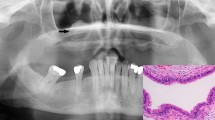

Bioinformatics analysis of gene expression profiling of human ACP whole tumours identifies modules of genes potentially associated with specific tumour cell compartments. a Representative histology of ACP samples showing and areas of tumour (T), reactive glial tissue (G), wet keratin/ghost cells (WK), epithelial whorls (C) (epithelial whorls referred to in this paper as clusters), palisading epithelium (PE) and stellate reticulum (SR). Immunohistochemistry using antibodies against β-catenin (β-cat) on case JA029 showing clusters of cells with nuclear-cytoplasmic accumulation. Scale bars 400 μm (top left panel), 100 μm (other three panels). b Scatterplot revealing a significant correlation between CTNNB1 mutation frequency and histologically assessed tumour content. # case JA011; * case JA005; controls: fetal pituitaries and NFPA tissues. See Suppl. Table 1 (Online Resource 2) for sample details. c Principal component analysis plot showing the separation between adamantinomatous craniopharyngioma (ACP), non-functioning pituitary adenoma (NFPA) and control fetal pituitary tissues (fetal). d Bar plot of selected statistically significant and differentially expressed genes, as assessed by DESeq2, in ACP tumours compared with control fetal tissue. Higher than 0 means higher expression in ACP and lower than 0 means higher in control tissue. The most up-regulated genes in ACP tumours are keratins. Other up-regulated genes include WNTs and WNT pathway targets (e.g. NOTUM, AXIN2, LEF1), genes known to be expressed in ACP (e.g. FGFs, BMPs) and previously suggested therapeutic targets (SHH, MMP12, MMP9, EGFR). Pituitary transcription factors (LHX3, POU1F1) and pituitary hormones (e.g. FSHB, GH1, TSHB) are up-regulated in controls. See Suppl. Table 3 (Online Resource 5) for details. Error bars = 1 standard error, *** adjusted p value < 1 × 10−9. e Multidimensional scaling plot of expression patterns of the 5000 most differentially expressed genes included in the weighted gene co-expression network analysis (WGCNA) analysis. The colour of each gene indicates it membership to a co-expressed gene expression module. f Heatmap of correlations between each module’s gene expression profile and phenotypic information. Scale bar indicate r value − 1 to + 1. For instance, the brown module shows a strong correlation with tumour content and mutational frequency, whilst the blue module correlates with the presence of glial reactive tissue and GFAP